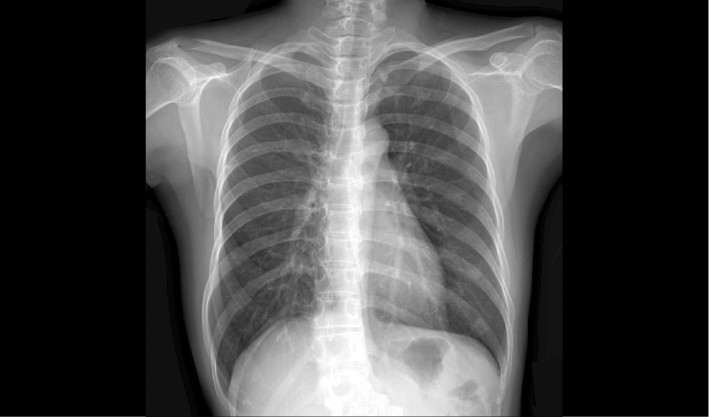

新东方1000F7系列搭载全自动智能机架,配合成熟优质的动态成像技术,全面实现DR摄影、动态透视功能,动静结合多视角观察病灶,减少漏诊误诊。

满足摄影,透视诊断需求

高清成像助力精准诊断